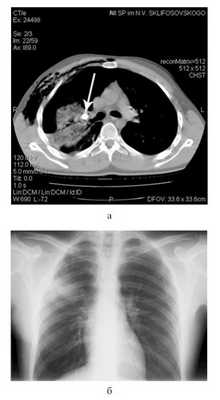

В связи с большим поступлением воздуха по дренажу сразу после этой операции пострадавшему выполнена КТ груди (рис. 6, а): Рисунок 6. Данные обследования пострадавшего Ш. а - компьютерная томограмма перед операцией; б - обзорная рентгенограмма груди перед выпиской из стационара. имелось инородное тело (пуля) в прикорневых отделах правого легкого, сдавливающее просвет верхнедолевого бронха. Травматическая инфильтрация II, III, VI, VII, VIII, IX, X сегментов правого легкого на фоне частичного коллабирования. Несмотря на наличие плеврального дренажа (по Бюлау), на фоне незначительного гемоторакса (230 см 3 ) имелся пневмоторакс большого объема (1100 см 3 ). Определялись эмфизема мягких тканей правой поверхности грудной стенки, перелом II и III ребер справа.

Под эндотрахеальным наркозом выполнена переднебоковая торакотомия в пятом межреберье справа. В плевральной полости около 400 мл крови. На переднебоковой поверхности верхней доли правого легкого в проекции III сегмента определяется рана диаметром 2 см, из которой обильно поступал воздух и немного крови. По краям дефекта имеется зона невентилируемой паренхимы легкого диаметром 3 см. В дне раны на глубине около 5 см находится инородное тело - пуля. Отмечается небольшое геморрагическое пропитывание ткани верхней доли легкого со стороны корня, кровотечения нет. Рана легкого расширена и пуля калибра 9 мм извлечена. В дне раны определялся сегментарный бронх (Б3) с боковым дефектом размером 3×6 мм с острыми углами. Дефект ушит нитью полидиоксанон 4/0 на атравматической игле. Дефект в легком послойно ушит викрилом 2/0. Гемостаз, аэростаз. Ателектазированные участки легкого расправлены. При дальнейшей ревизии выявлен перелом ребра в области огнестрельной раны с подтеканием крови. Произведено лигирование с прошиванием межреберной артерии. Плевральная полость дополнительно дренирована во втором межреберье по среднеключичной линии, рана грудной стенки послойно ушита. Интраоперационная кровопотеря около 1000 мл, кровь реинфузирована аппаратом Сell-saver.